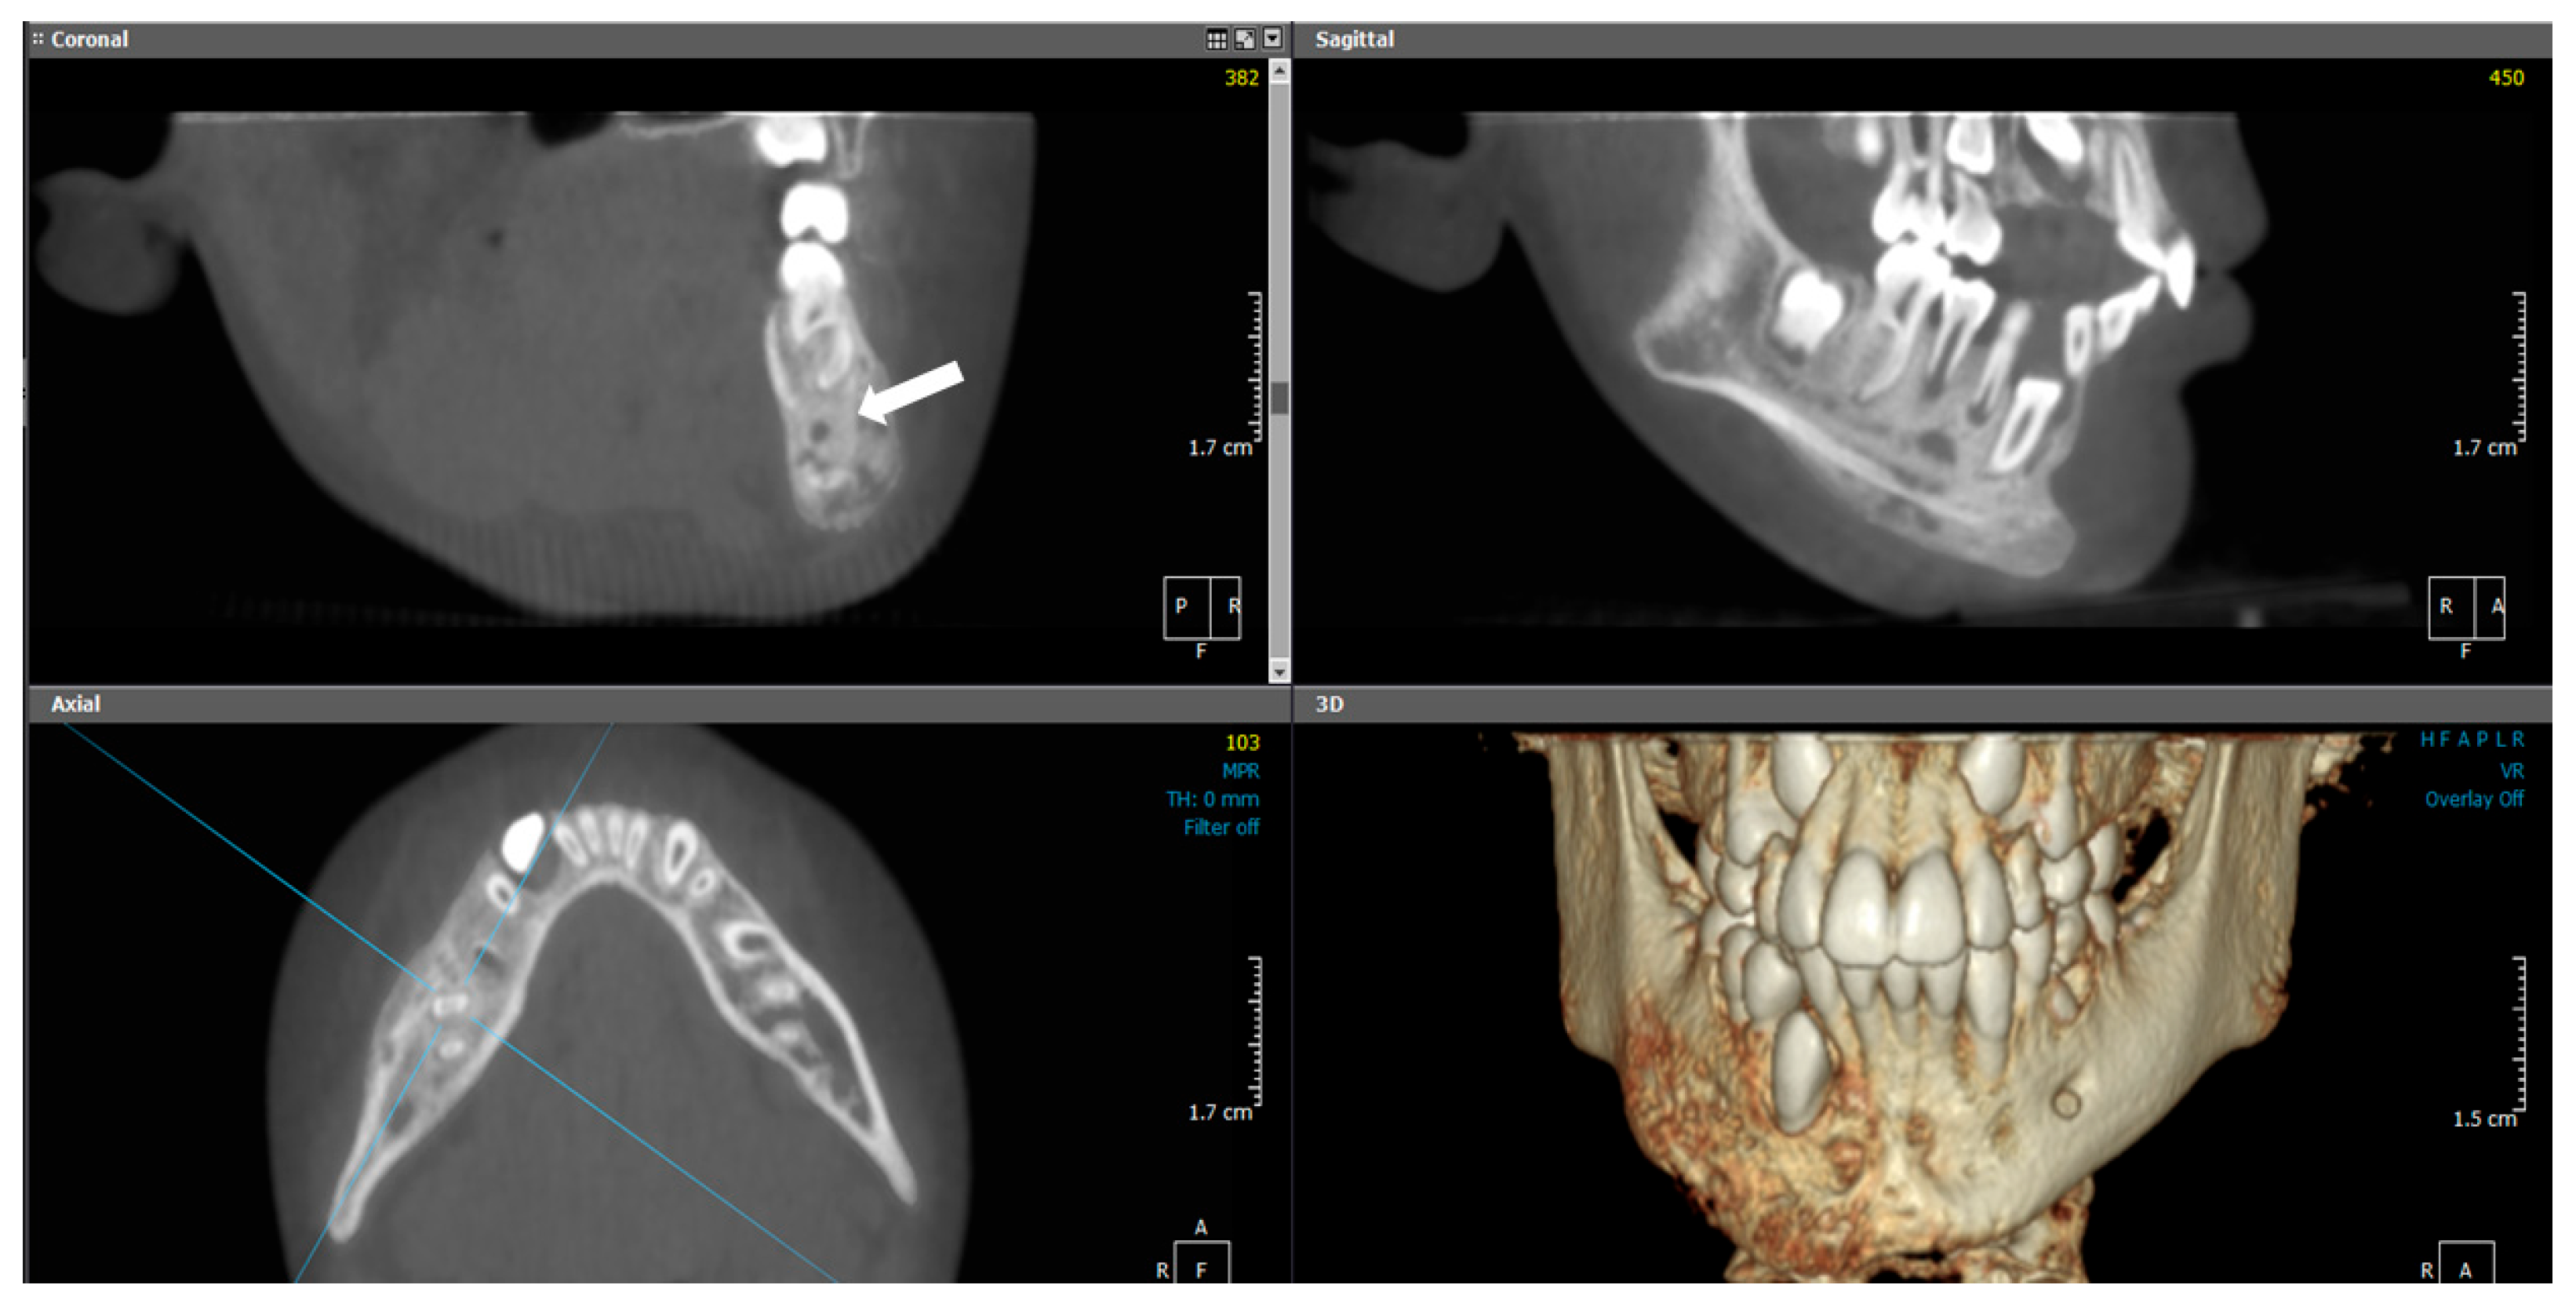

2.1.2. Radiographic Examination

| 1 | 11 | Left mandible (#32–#37) | Mixed sclerotic and lytic lesion with buccolingual expansion and “onion-skin” periosteal reaction | Irregular bone and fibrous tissue, sclerosis, no inflammation or bacteria | Long-term antibiotic course, NSAIDs | CNO confirmed by imaging, histology, and initial failure to respond to antibiotics | Conservative; antibiotics discontinued after improvement | Improved at 7 months; recurrence at 18 months; no further treatment needed |